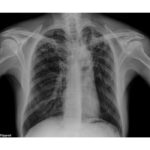

Boosting TB Detection with AI

Harnessing cutting-edge technology, the AI-Mounted Digital X-ray for TB Screening is transforming early and accurate detection in Ethiopia, recently we concluded a 3-day “Basic Training on the AI-Mounted Digital X-ray for TB Screening & Detection” for 30 participants, including REACH Ethiopia Urban TB officers & healthcare workers in Addis Ababa. The session provided hands-on training […]

Kidus Petros Specialized Hospital, the national center of excellence for DR-TB care, in collaboration with Urban TB LON II Project, supported by the US government has stepped up its DR-TB Prevention and care services by conducting retrospective household contacts screening using AI-Powered CXR systems and initiation of DR-TB Preventive Therapy (DR-TB TPT) for eligible household […]